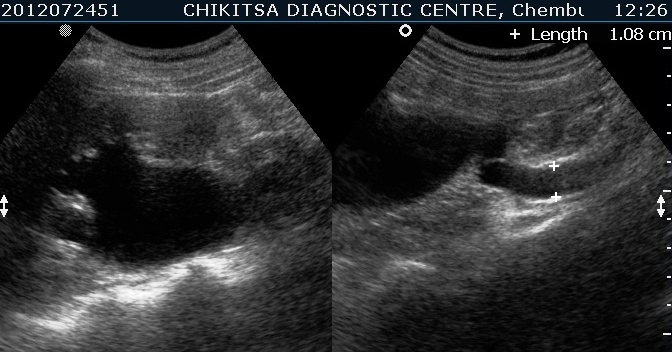

July-Aug 2012 :

Left kidney shows hydronephrosis.

Lesion in the wall of the urinary bladder has increased in size. Calcific areas are noted. Urinary bladder malignancy ( confirmed by histopathology), possibly following schistosomiasis.